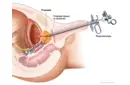

Ameliyat Türleri Orta kulak iltihabı tedavisinde uygulanan başlıca cerrahi yöntemler şunlardır:

Ameliyat Riskleri Her cerrahi müdahale gibi, orta kulak iltihabı ameliyatının da bazı riskleri bulunmaktadır. Bu riskler arasında şunlar yer almaktadır: